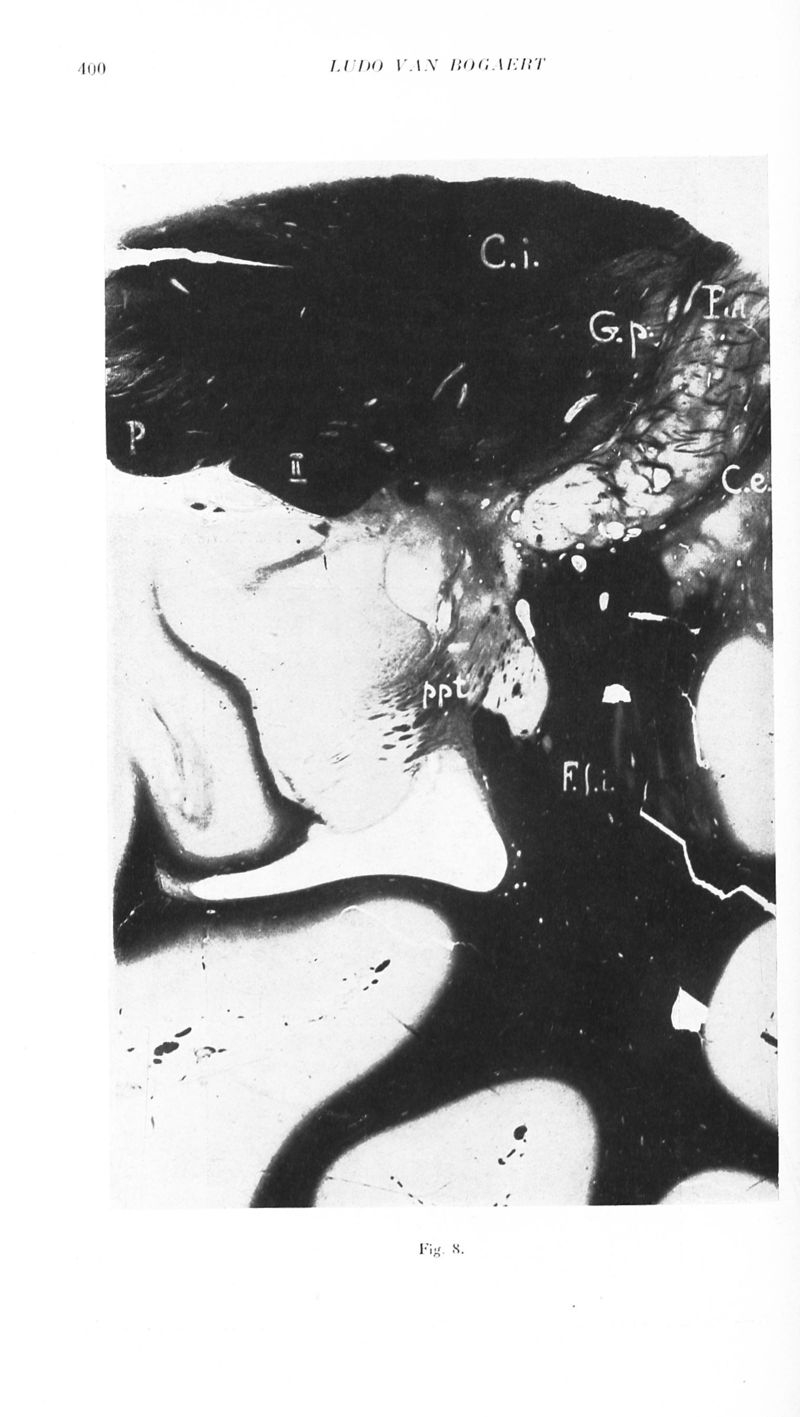

Revue neurologique

1929, vol 2. - Paris : Masson , 1929.